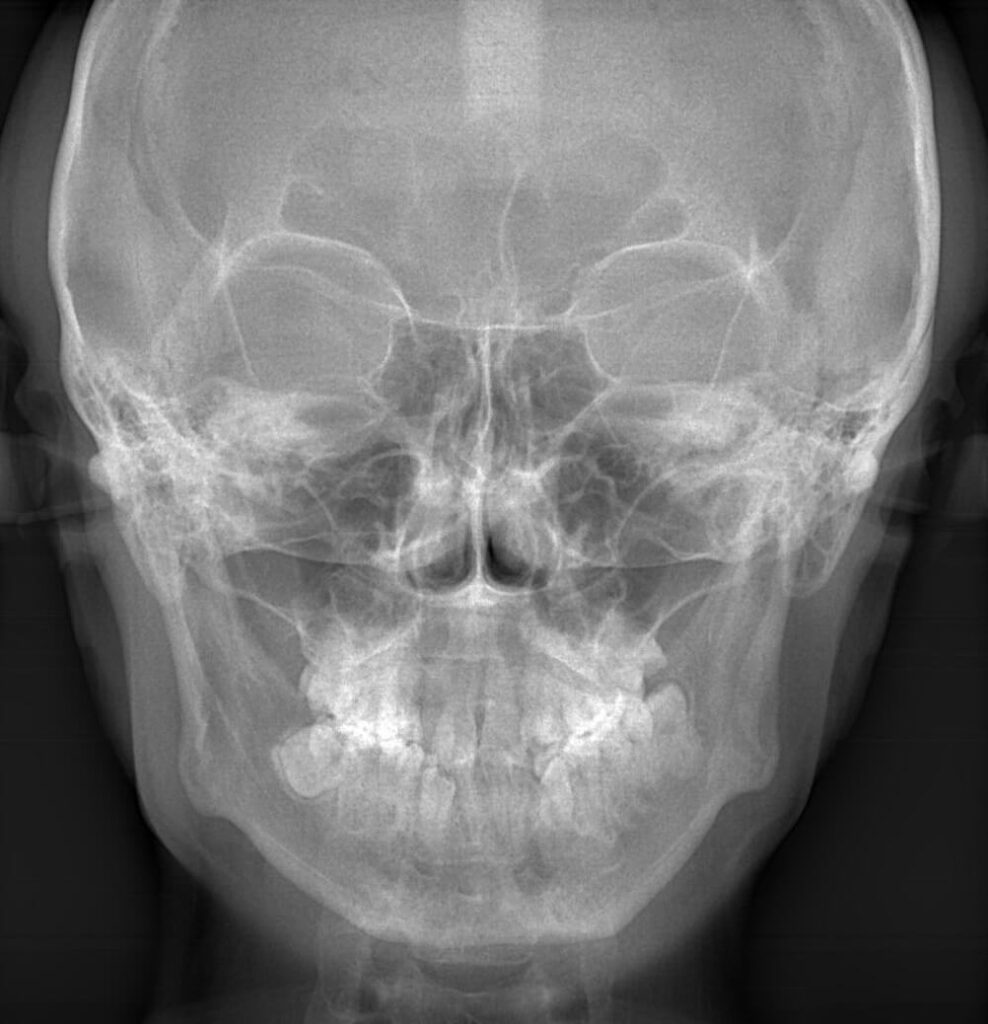

口腔の「外科処置」を行います。

基本的なものは親知らずの抜歯です。

特に下アゴの親知らずの周囲には太い神経および血管が存在し、抜歯には細心の注意が必要となるケースが多々あります。

また、アゴの中の予期せぬ場所に歯が埋まり、他の歯に悪影響を及ぼすことから困難な抜歯を行う場合もあります。

その他、アゴの痛み、口が開きにくい、骨折、インプラント、大きな膿の袋、良性および悪性腫瘍の出現などの対応も口腔外科の分野です。